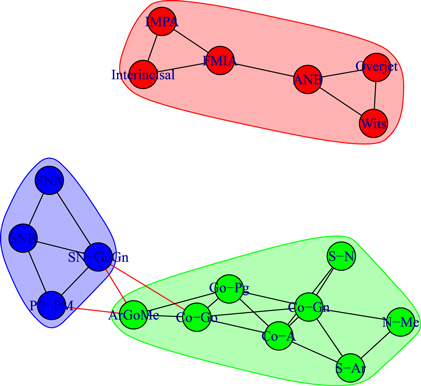

Standard image High-resolution imageFinally, figure 5 illustrates the correlation network of the cephalometric characteristics of the cohort of the untreated Class III controls of 11–18 years of age (U2).

Figure 5. Network analysis of the Class III untreated control subjects (U2, 11–18 years of age).

Standard image High-resolution imageWhile the network of treated patients at the end of RME/FM therapy showed a highly interconnected structure between dentoalveolar adaptive and skeletal variables (figure 4), the network of control patients exhibited two separate sub-networks pertaining to skeletal (left) and dentoalveolar (right) adaptive nodes (figure 5). The core of the network of treated patients consisted of a triangle composed by three maxillomandibular divergence variables: SN-GoGN, ArGoMe, and PP-MP. These variables seem to act as a bridge between skeletal features of Class III malocclusion and the dentoalveolar adaptive components of the craniofacial system.

We detect modules by applying the walktrap algorithm [42] on the complete graphs corresponding to consider all the possible edges weighted with their correlation rij; in particular, we use the igraph [44] implementation of the function walktrap.community of R [45]. To compare the results with the empirical outcomes of section 3.1, we show in all the pictures only links with a correlation correlation  and only nodes connected by such links. The analysis of the modules shows interesting differences among the three groups of patients: in fact, the modules characterising the networks of the patients before control (T1) and the untreated control patients (U2) share a similar structure (see figures 6 and 8) with three modules composed by analogous nodes. In fact, like in figure 3, the modules of T1 shown in figure 6 correspond to dentoalveolar adaptive nodes (top right of the picture), to skeletal horizontal nodes (bottom right of the picture) and skeletal vertical nodes (left of the picture); a similar correspondence exists among figures 5 and 8. Notice that for both T1 and U2 the modules are either separated or linked by negative links, indicating that such groups of nodes work as separate, non interacting, oro-facial modules. On the other hand, the network of treated patients (T2, figure 7) shows more modules ; apart to the new (respect to T1 and U2) isolated community formed by overjet and overbite (whose correlation is due to the successful action of the braces), the remaining communities are much more interlinked, possibly hinting a harmonization of the orofacial modules that start working together thanks to the orthodontic correction.

and only nodes connected by such links. The analysis of the modules shows interesting differences among the three groups of patients: in fact, the modules characterising the networks of the patients before control (T1) and the untreated control patients (U2) share a similar structure (see figures 6 and 8) with three modules composed by analogous nodes. In fact, like in figure 3, the modules of T1 shown in figure 6 correspond to dentoalveolar adaptive nodes (top right of the picture), to skeletal horizontal nodes (bottom right of the picture) and skeletal vertical nodes (left of the picture); a similar correspondence exists among figures 5 and 8. Notice that for both T1 and U2 the modules are either separated or linked by negative links, indicating that such groups of nodes work as separate, non interacting, oro-facial modules. On the other hand, the network of treated patients (T2, figure 7) shows more modules ; apart to the new (respect to T1 and U2) isolated community formed by overjet and overbite (whose correlation is due to the successful action of the braces), the remaining communities are much more interlinked, possibly hinting a harmonization of the orofacial modules that start working together thanks to the orthodontic correction.

Download figure:

Standard image High-resolution imageFigure 8. Module repartition of the Class III control subjects (U2). As in figure 6, the detected modules correspond to dentoalveolar adaptive nodes (top right—red), to skeletal horizontal nodes (bottom right—green) and skeletal vertical nodes (bottom left—blue).

Standard image High-resolution imageHence, the arrangement of modules of at the start (T1, figure 6) and at the end of treatment (T2, figure 7) of the same Class III patients confirms the strict interlinked module topology after RME/FM treatment, as compared with untreated controls (U2, figure 8).